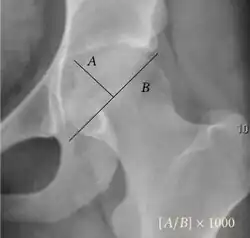

- Reimer's migration index (MI), also called the femoral extrusion index,[3] is calculated if hip dysplasia is detected. It can be used to indicate hip dislocation. It is the horizontal distance (parallel to the Hilgenreiner Line) between the Perkin line and the lateral border of the ossification center of the femoral head, divided by the horizontal width of the ossification center. The migration index is normally less than 33% by most sources,[9] but 25% and 30% has also been suggested.[10]